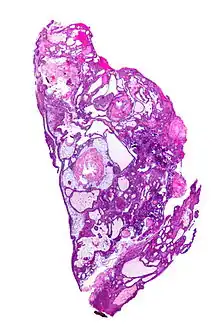

On macroscopic examination, craniopharyngiomas are cystic or partially cystic with solid areas. On light microscopy, the cysts are seen to be lined by stratified squamous epithelium. Keratin pearls may also be seen. The cysts are usually filled with a yellow, viscous fluid rich in cholesterol crystals. Of a long list of possible symptoms, the most common presentations include headaches, growth failure, and bitemporal hemianopsia.

Micrograph showing the characteristic features of an adamantinomatous craniopharyngioma - cystic spaces, calcifications, and "wet" keratin, HPS stain